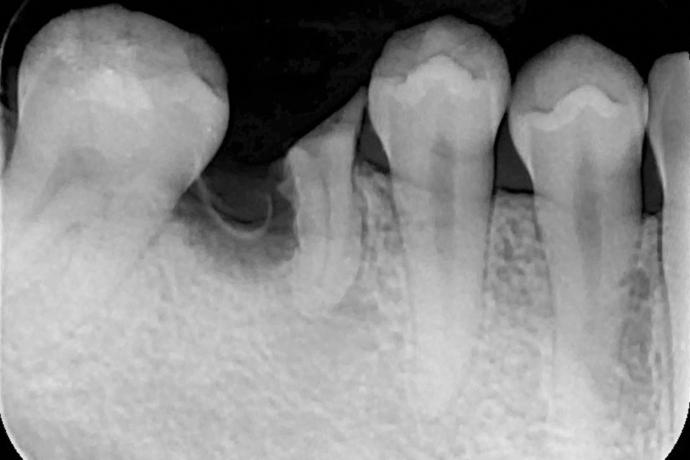

術中-

拔除殘根並立即植入人工牙根